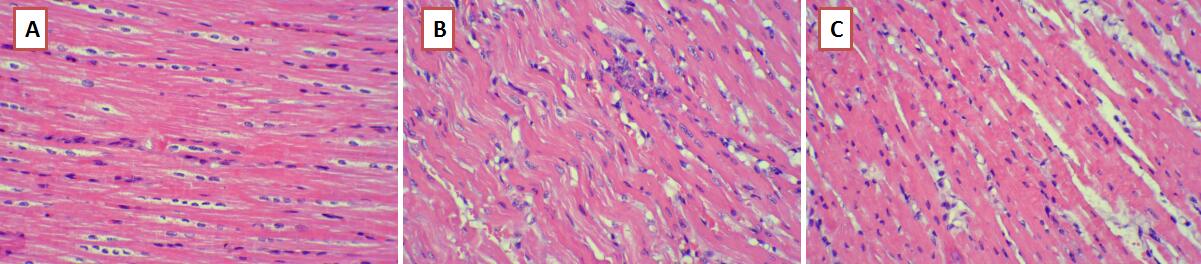

HE染色结果显示,假手术组心肌细胞膜完整,心肌纤维走行整齐,无炎性细胞浸润,心肌组织未见明显病理改变。对照组心肌细胞膜损伤,心肌纤维排列紊乱,细胞胞浆深染,心肌纤维断裂伴有大量炎性细胞浸润。与对照组相比,硝酸异山梨酯组心肌细胞变性程度以及炎性细胞浸润程度均有所减轻(图 1)。

| A:假手术组心肌细胞膜完整,心肌纤维走行整齐,无炎性细胞浸润。B:对照组心肌细胞膜损伤,心肌纤维排列紊乱,细胞胞浆深染,心肌纤维断裂伴有大量炎性细胞浸润。C:硝酸异山梨酯组心肌细胞变性程度以及炎性细胞浸润程度均有所减轻 图 1 心肌HE染色(×200) Fig 1 HE stain of cardiac tissue (×200) |